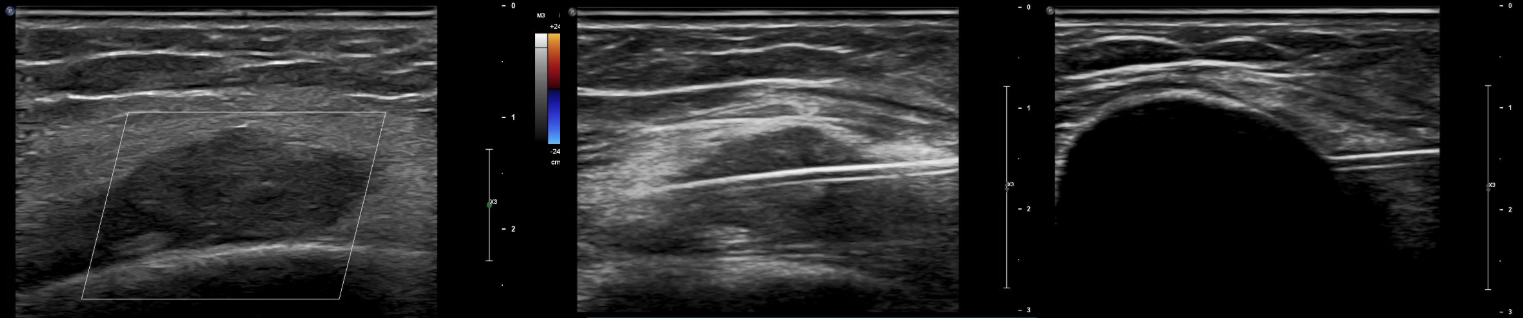

A symptomatic venous malformation is treated with cryoablation using ultrasound guidance. The left image shows the lesion under ultrasound. The middle image shows placement of a cryoprobe through the lesion. The right image shows formation of an ice ball completely covering the lesion.